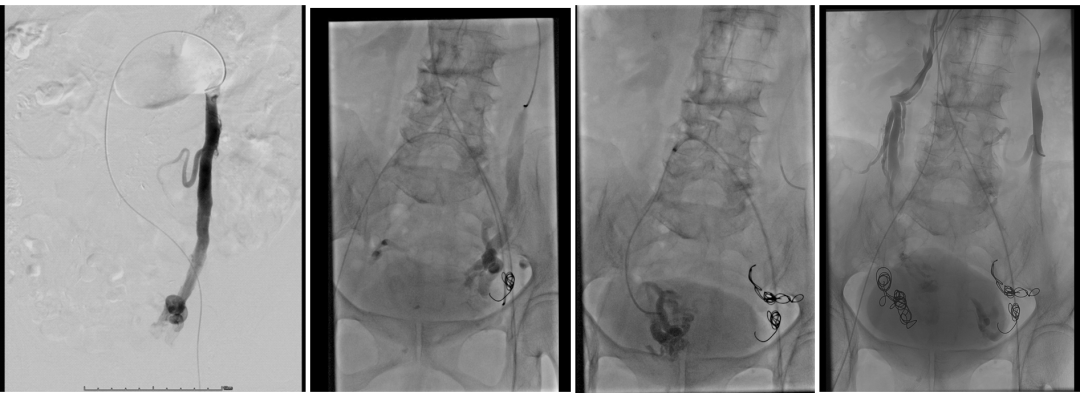

中山经验:“节约型三明治技术”

Sandwich技术优化-节约版

GLUBRAN替代Onxy;

双股静脉入路:可调弯鞘解决反流支;

减少可控圈以及微导管使用;

减少费用;

减少照射;

减少移位;

减少复发;

需解决技术问题:液体栓塞材料溢流。

示例(D-IIV)

示例(LOV+LCV)